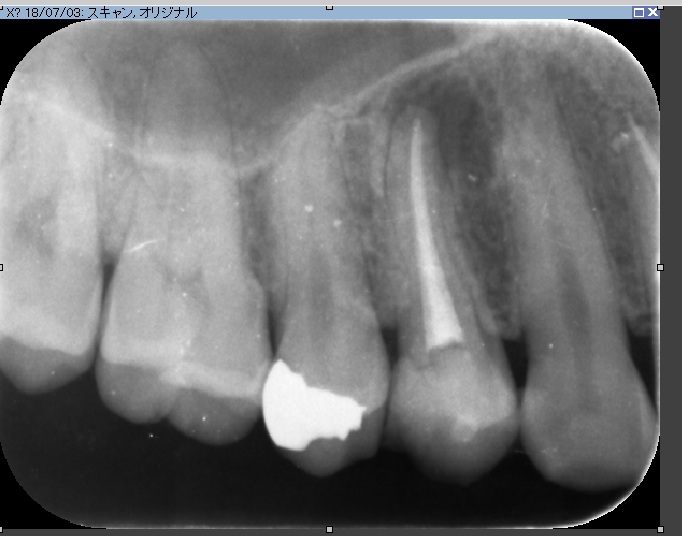

術前

術後